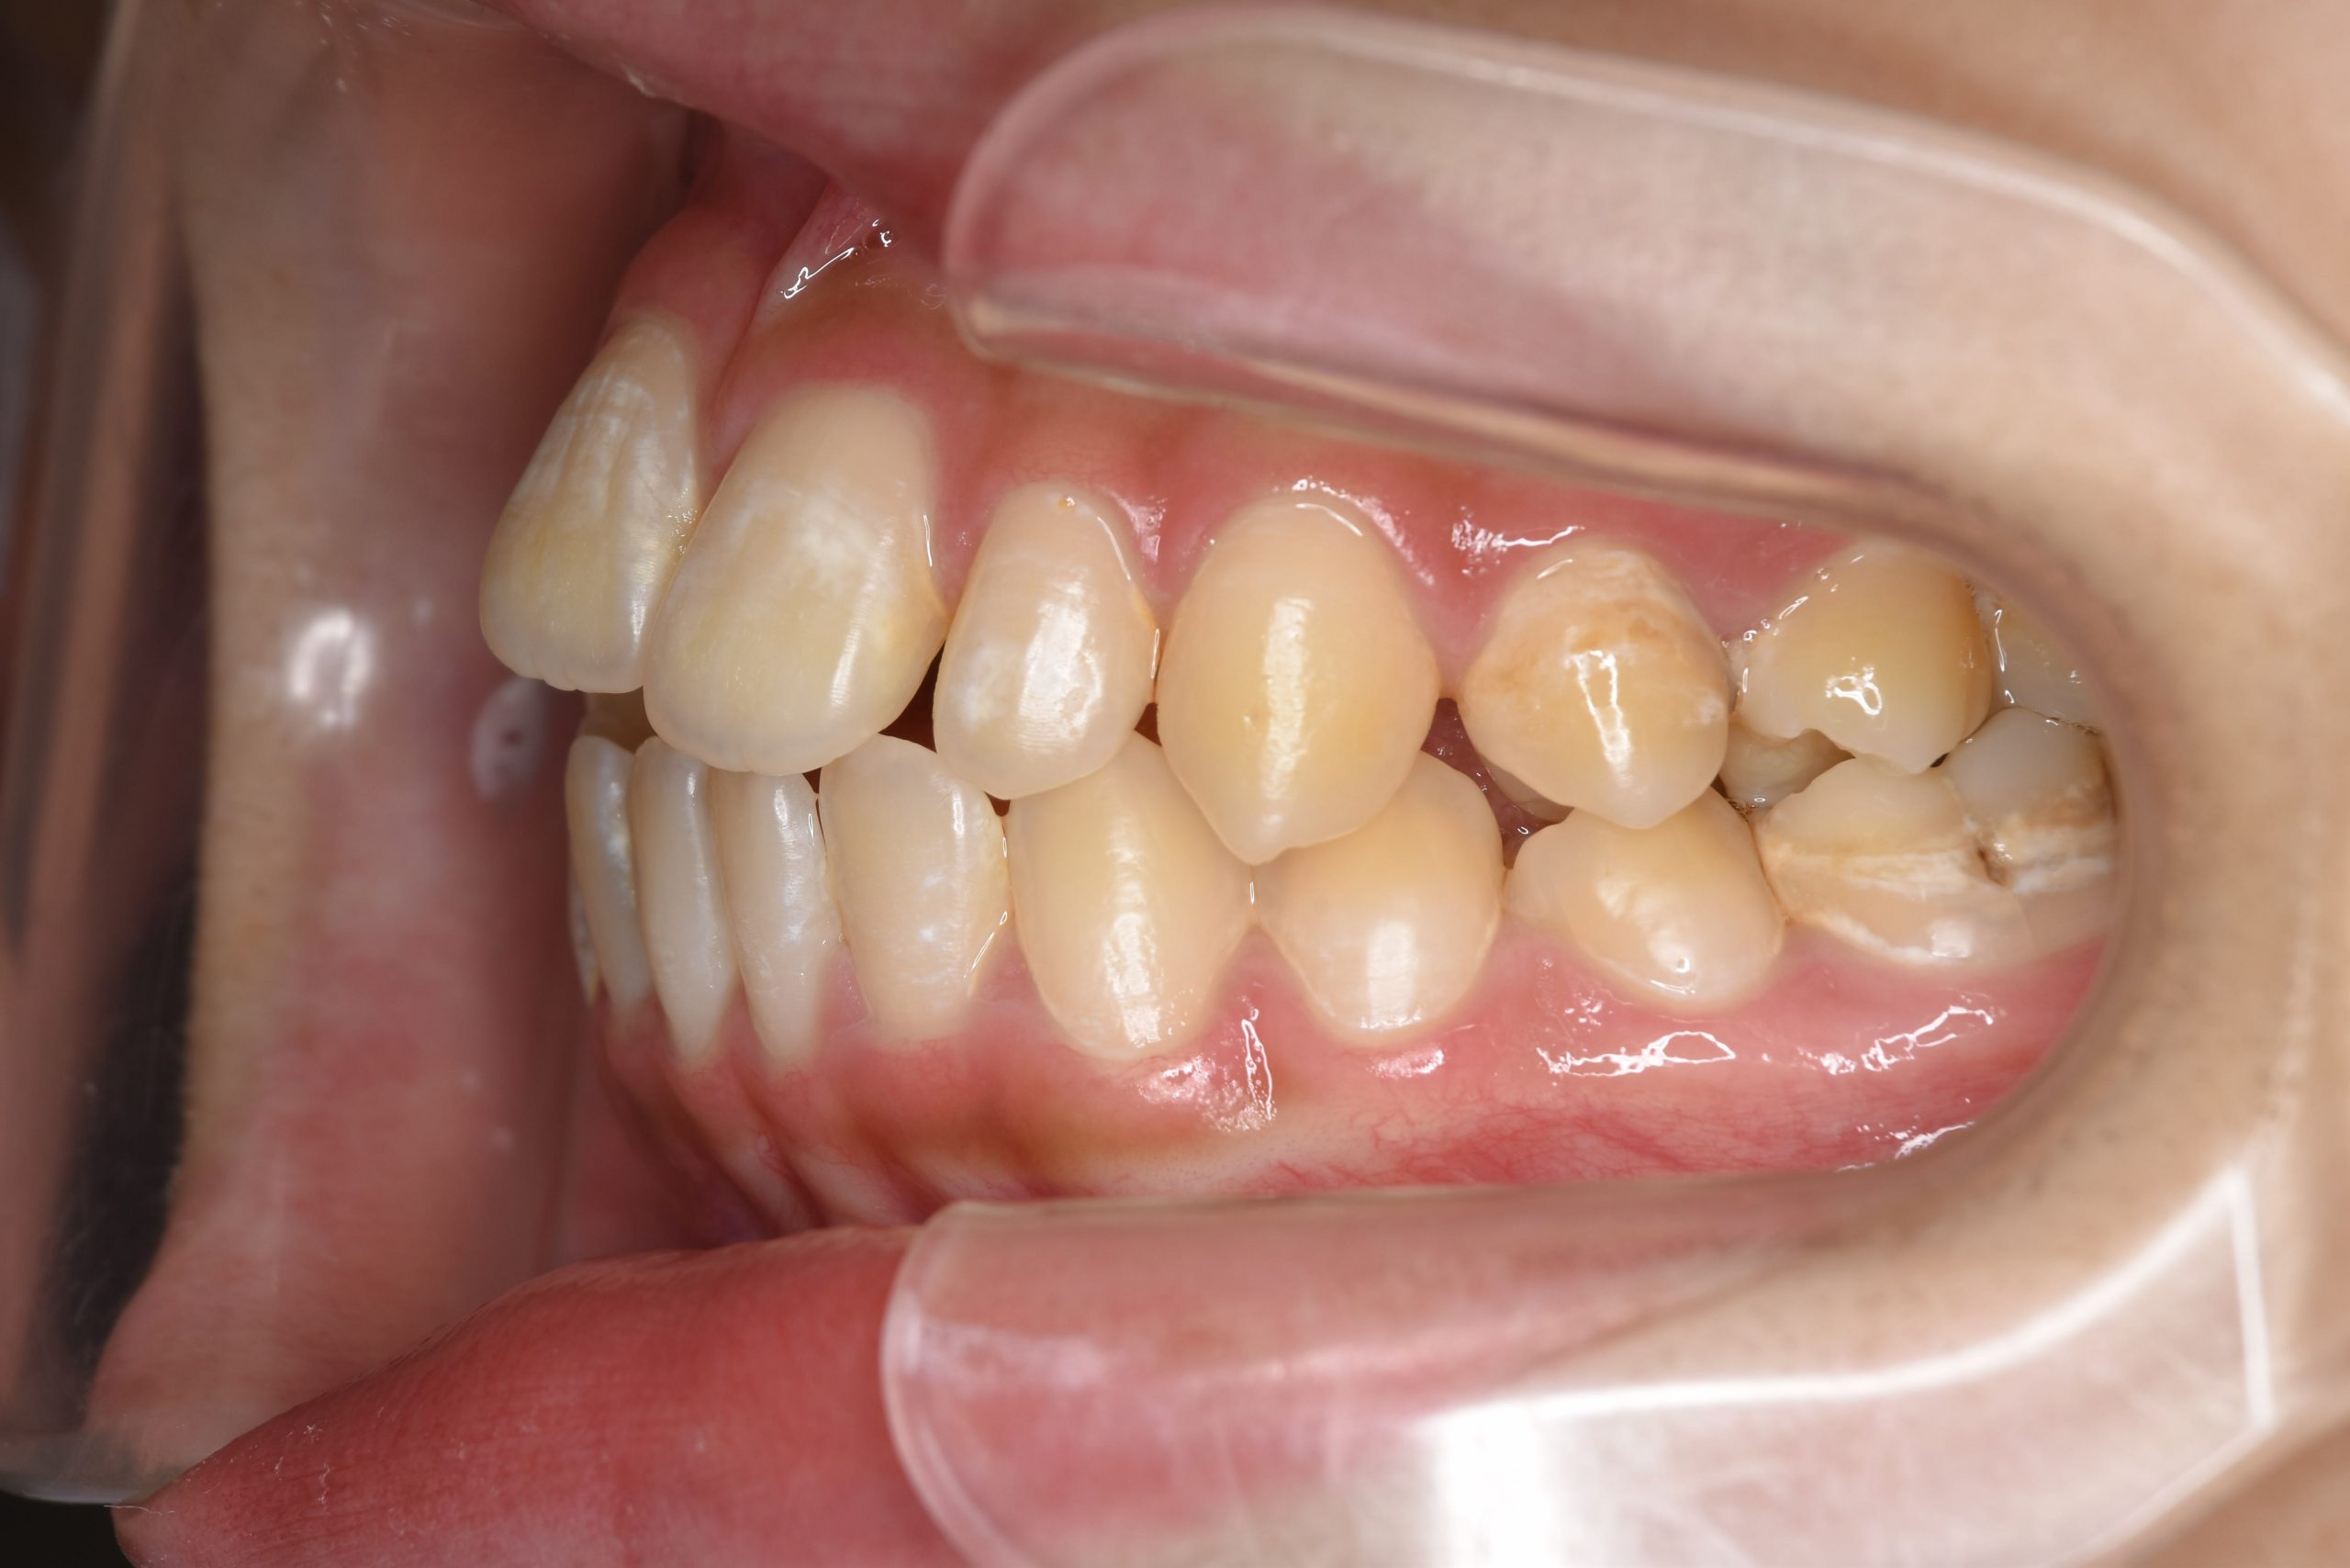

ビフォー

ワイヤー矯正治療|症例_032

主訴 歯並び|かみ合わせ

施術内容 MSEと下顎リンガルアーチを用いて上下顎骨を拡大した。

その後マルチブラケット装置を用いて非抜歯で歯牙を配列し良好な咬合を獲得した。

吸指癖と鼻閉症状は改善した。